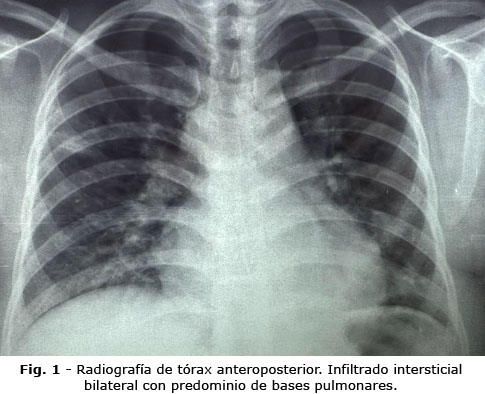

A las 72 horas presentó dificultad respiratoria aguda, con gasometría alterada (PaO2: 32 mmHg, PaFiO2: 153 mmHg). Se inició oxigenoterapia con cánula binasal (5 L/min). La radiografía torácica mostró infiltrados intersticiales bilaterales. A las 96 horas, el hematocrito descendió (24 %), con aumento de bandas (13 %) e hipoalbuminemia (2,5 mg/dL). Debido al empeoramiento respiratorio, se cambió a cánula de alto flujo (FiO2: 45 %). La radiografía de control reveló patrón alveolo-intersticial y aumento del índice cardíaco (0,6), confirmándose derrame pericárdico por ecocardiografía (Fig. 1).